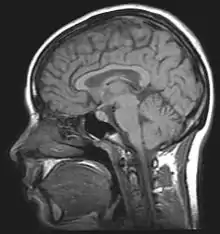

MRI

An MRI (magnetic resonance imaging) scan is an imaging test that uses powerful magnets and radio waves to create pictures of the body. It does not use radiation. Single MRI images are called slices. The images can be stored on a computer or printed on film. One exam produces dozens or sometimes hundreds of images. To locate nerve palsy, MRI is used by physicians to detect the position and location of damaged peroneal nerve.[10]